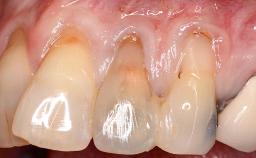

Implant Placement in the Esthetic Zone and Coverage of Multiple Gingival Recessions

This case illustrates use of a modified ‘tunnel’ technique, which has been shown to be highly effective in root coverage procedures. The tunnel technique is used to achieve soft-tissue augmentation across the anterior area, including the planned implant site, using collagen matrix as grafting material. The patient is a 47-year-old woman with high esthetic expectations. Her main concern was the appearance of the anterior teeth and their “elongation”.

Soft Tissue Contour and Volume Significantly deficient